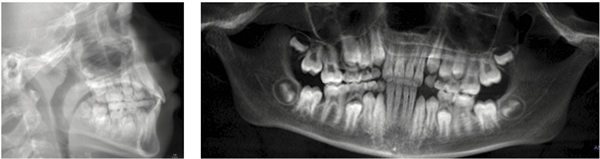

The panoramic radiograph revealed mixed dentition appropriate for the patient’s age, with developing permanent dentition in normal eruption sequence. No pathology was identified (Fig. 4).

Fig. 4: Initial panoramic radiograph and lateral cephalogram confirming mixed dentition, Class I skeletal pattern, and normal root development.

Post-treatment radiographs confirmed no adverse root resorption or alveolar bone changes attributable to treatment. Cephalometric superimposition showed favorable dentoalveolar changes consistent with the treatment objectives, with stable skeletal relationships (Fig. 8).

Fig. 8: Final lateral cephalograms and panoramic radiographs. Cephalometric superimposition confirmed favorable dentoalveolar changes with no adverse root or bone findings.